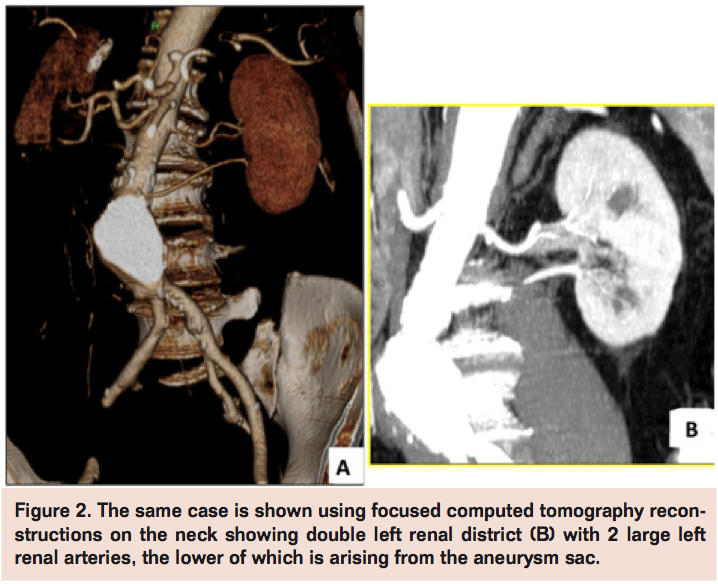

The decrease in open surgery volume for AAA repair in the last decades after the introduction of EVAR is mainly justified by well-demonstrated, consistently lower perioperative risks with new mini-invasive techniques despite the more uncertain durability often requiring reinterventions.9,10 Development of more advanced technologies and devices (fenestrated, branched stent-graft, etc.) progressively expanded the range of suitability for endovascular approaches also in the presence of more challenging and adverse AAA anatomies, such as large and angulated necks, small iliac arteries, and extensive aneurysms. Nevertheless, morphology is still the main and probably irreversible reason of concern for EVAR. Forced application of EVAR when not suited for AAA morphology (Figures 1-4) produces increased failure and complication rates. Schanzer et al reviewed outcomes of 10,228 EVAR performed in a 5-year period in the U.S. and found that only 42% of patients had an anatomy that met the most conservative definition of device instructions for use. The 5-year post-EVAR rate of AAA sac enlargement was exceptionally high at 41%. Notably, the rate of AAA sac enlargement was significantly higher in patients who underwent EVAR outside the instructions for use.11 Therefore, despite the feasibility in deployment, long-term efficacy of EVAR in forced AAA anatomies remains a main drawback allowing these cases to be better pursued by an open surgical approach.

Thereby, open aneurysm repairs are currently performed primarily in patients with more extensive aneurysms or who are not anatomically suitable for EVAR with the main limitation being an anatomically unfit proximal neck (short, large, thrombosed, angulated) or in patients with EVAR failure (eg, conversion after stent-graft migration, persisting endoleak with aneurysm growth, stent-graft rupture, etc.). Severe vessel calcification, iliac access obstruction, extensive iliac aneurysm extension, and previous aortic graft infection are other common findings in AAAs mainly reserved today for open surgery. These anatomical changes may also pose higher technical challenges for open surgery, such as raised frequency of suprarenal clamping or visceral revascularization and increases in operative duration, use of blood products, intensive care unit stay, hospital length stay, and overall complication rates when compared to repairs in more straightforward and infrarenal AAA, now routinely treated by EVAR.